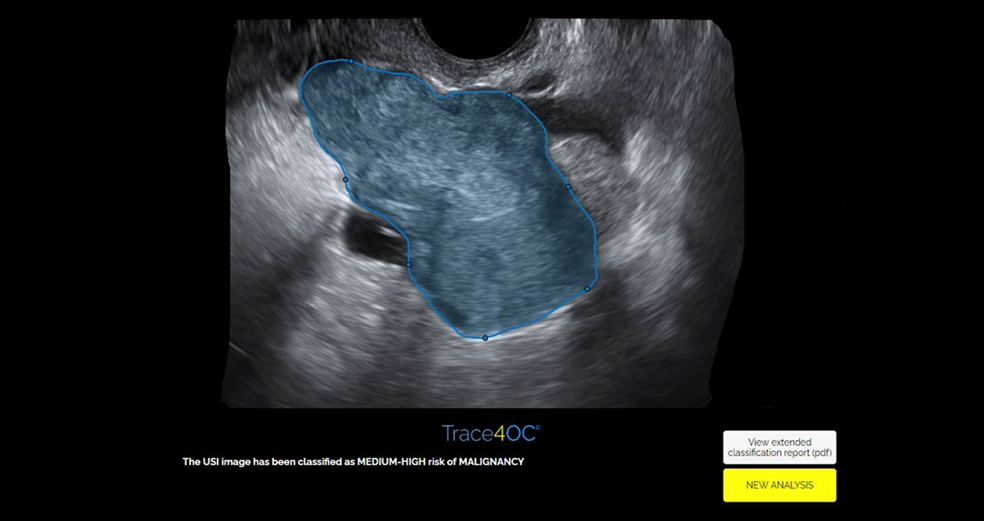

DeepTrace Technologies, the Italian spin-off of the University School for Advanced Studies IUSS Pavia, that has recently secured a seed funding round of 1,7M euros by Progress Tech Transfer, announces the launch in Europe of the CE marked TRACE4OC™, a vertical AI-powered tool developed with the proprietary, patented-protected AI platform TRACE4™, able to select women with high-risk of ovarian cancer by a simple automatic reading of transvaginal ultrasound scan and serum level of CA 125.

TRACE4OC™ is indicated for women at risk of ovarian cancer under the recommendation of gynecology specialists. Physicians with expertise in pelvic ultrasonography (US) can use TRACE4OC™ to support the reporting of US-detected adnexal masses investigations. Specialists in gynecology can use TRACE4OC™ as an aid to diagnosis. TRACE4OC™ software provides the subject level of risk (very-low-risk or medium/high risk) of being affected with ovarian cancer at the date of the TRACE4OC™-processed US investigation of an adnexal mass, combined with the serum level test for Cancer Antigen 125 (CA-125), performed no earlier than and no later than one month from the US study, and with the current woman’s menopausal state (premenopause or postmenopause). TRACE4OC™ showed sensitivity >97%, specificity >75%, PPV >86%, NPV >97%, moreover its performance improves with time, as the training of the tool progresses. DeepTrace Technologies considers TRACE4OC™ as a support to gynecology specialists in their diagnosis, and as a support to physicians with expertise in pelvic US in their reporting of adnexal masses. These medical professionals retain the final decision-making responsibility.